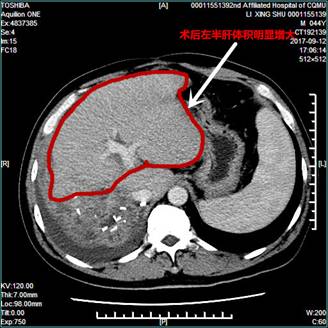

经充分准备后,治疗小组顺利实施该手术,患者按预期安全度过围手术期。本次复查CT显示,左半肝明显增大,且无肿瘤复发征相。显然ALPPS手术方式为部分不能耐受大范围肝脏切除的患者提供了生存的机会,而腹腔镜技术则通过微创化极大的减轻了患者对两次手术的恐惧,极具推广价值。不过,要在腹腔镜下完成不离断肝蒂的原位半肝劈离,难度远超过腹腔镜右半肝切除术,需要极其娴熟的腔镜肝切除经验与技术。该例患者的顺利恢复,标志着在全院领导、相关处室同事的大力支持下,我院肝胆微创外科团队经近两年的不懈努力,其技术水平已逐渐成熟。